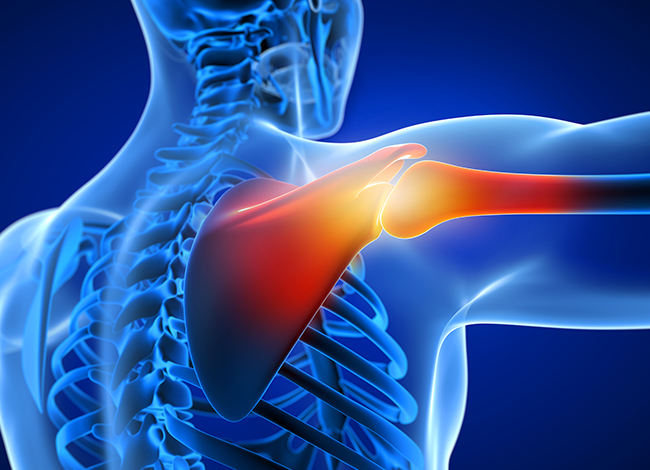

어깨 인공관절 치환술

어깨 관절의 손상 정도가 심하여 더 이상의 자기 관절을 살릴 수 없는 경우에 손상된 관절면을 제거한 후 금속과 특수 플라스틱으로 이루어진 인공관절을 삽입하며 통증을 없애고 관절운동 기능을 회복시키는 수술.

- 적응증

· 상완골두가 심하게 골절이 되어 복원이 어려울 경우.

· 봉합이 불가능한 회전근개 파열의 경우.

· 상완골두의 무혈성 괴사가 있는 경우.

· 각종 관절염으로 인해 관절이 완전히 파괴되고 약물요법 및 주사요법으로도 증상이 완화되지 않을 때.